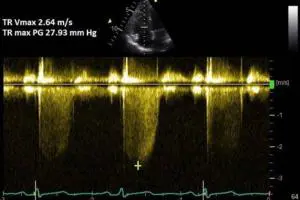

فشار ریه در اکو نشانه چیست؟ برای تشخیص فشار ریه به کدام دکتر مراجعه کنیم؟ درمان بالا بودن فشار ریه چیست؟ درمان جدید فشار خون ریوی در ادامه مطلب. برای اطلاعات بیشتر و مشاوره رایگان در این مورد منتظر تماس سفیر سلامت بهار زندگی باشید.